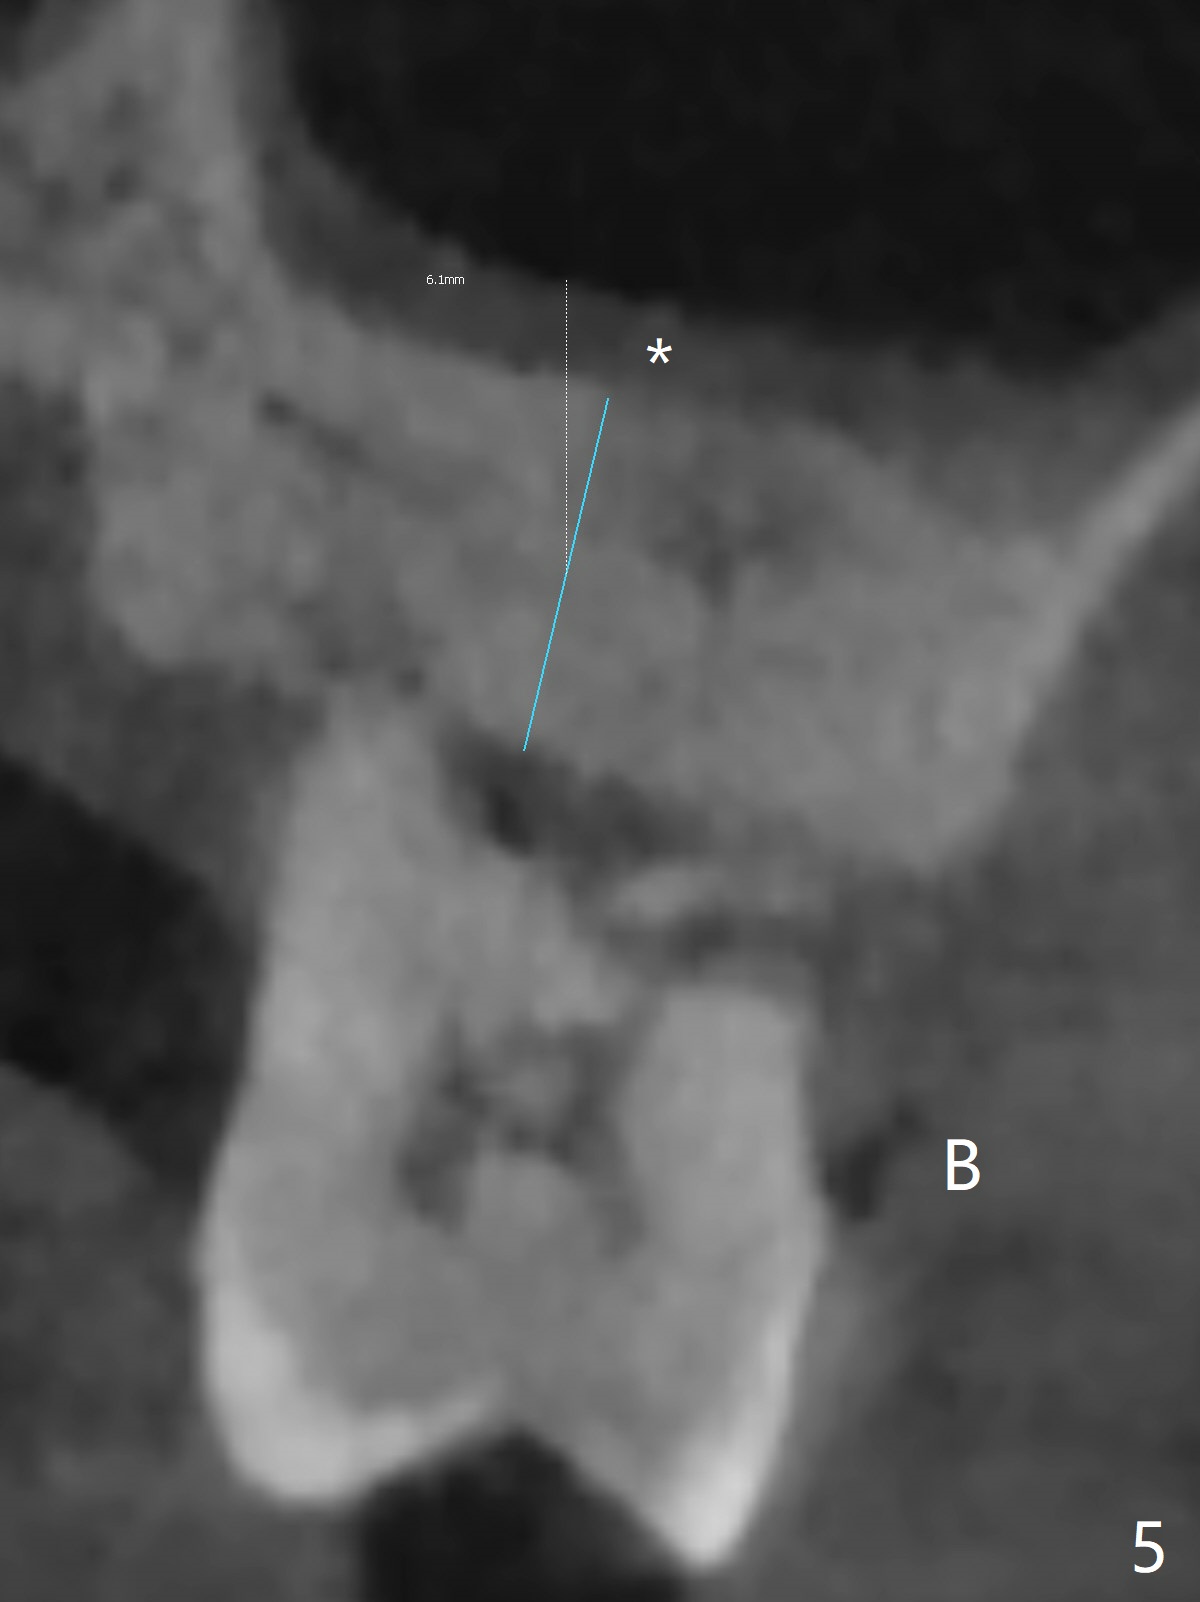

A 60-year-old man had buccal furca abscess at #14 with an unknown radiolucent lesion within the tooth five months earlier (Fig.1 *). Now the tooth is sensitive to cold. CBCT shows internal resorption involving the mesiobuccal and distobuccal roots (Fig.3,4 (axial section) *) with exits mesially (Fig.3 >) and buccally (Fig.2 ^). There is periapical radiolucency of MB (Fig.3,7) with the thickened overlying sinus membrane (Fig.3,5,6 (*), as compared to that over the tooth #3 (Fig.6)). Osteotomy will be established in the septum away from the lesion (Fig.8 red circle) and for 5 mm (Fig.5 (coronal section)). He is a heavy bruxer, loosening Ketac-cemented unipost. Use PRF to repair the defect associated with the MB lesion and sinus lift.